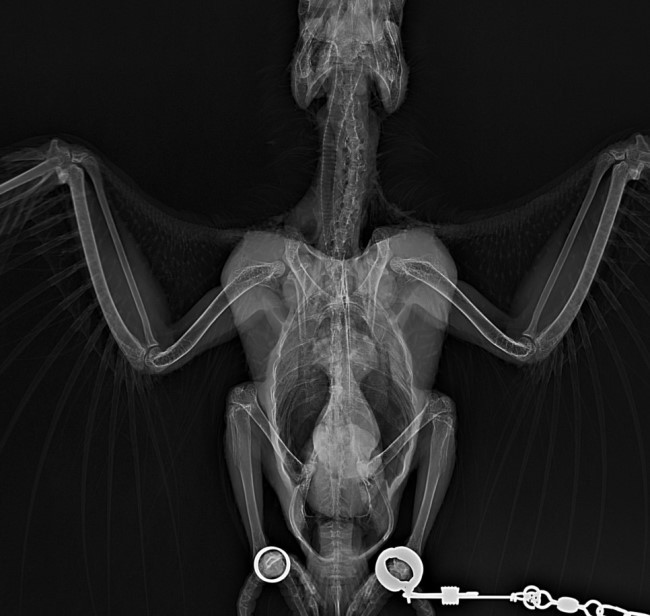

¿ì¸® ¾Ö°¡ °É¸° º´Àº

Àå±â°¡ ¿µ¾çºÐ Èí¼ö¸¦ ¸øÇؼ Á¡Á¡ ¸»¶óÁ×´Â º´ÀÓ

º¸Åë ¾Þ¹«»õ´Â Àå±â°¡ »çÁøÃ³·³

¸ð·¡½Ã°è ¸ð¾çÀÌ µÇ¾î¾ß °Ç°ÇѰǵ¥

¿ì¸®¾Ö´Â ÁøÂ¥ Àå±â°¡ ÀÜ¶à ºÎ¾î¼ ºó °ø°£ÀÌ ¾ø¾úÀ½

È£Èí±â°¡ ´·Á °³±¸È£Èí ÇÏ´Â Á¤µµ±îÁö °¨

3ÁÖ Àü Âë¿¡ 130±×¶÷ÀÌ 105±×¶÷±îÁö ºüÁ³´Âµ¥

2ÁÖ ÀüºÎÅÍ Â÷Ãû ȸº¹ÇÏ´õ´Ï

¾ÆÄ§°øº¹ 117±×¶÷±îÁö ´Ù½Ã ¿Ã¶ó°¨!

ÀÌÁ¦ ¿¢½º·¹ÀÌ¿¡ ºó °ø°£ÀÌ º¸ÀÏÁ¤µµ·Î

Àå±â°¡ ºÎÀº°Ô °¡¶ó¾É¾Ò´ë

Ä¡»çÀ²ÀÌ 80ÇÁ·Î ÀÌ»óÀÎ º´À̶ó